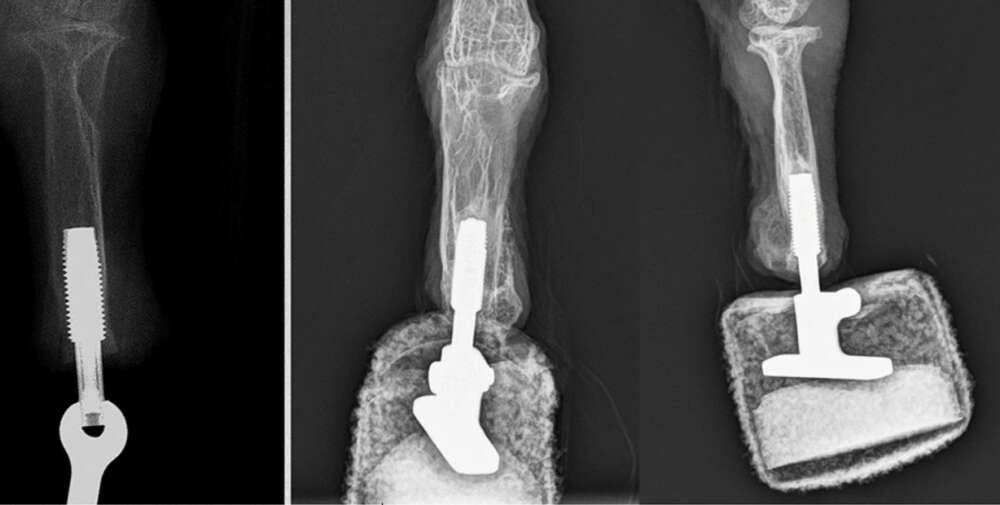

La prótesis se hizo en el Departamento de Cirugía Plástica, Reconstructiva y Estética de MedUni en Viena. Según explican, la extremidad depende de una nueva técnica conocida como osteointegración en la que la prótesis se conecta directamente a un hueso, lo que proporciona una mejor estabilidad a la extremidad de reemplazo.

En el artículo recientemente publicado en Scientific Reports cuentan que la operación de Mia para colocar un implante que pudiera anclar la prótesis al hueso de su propia pierna fue un éxito y que, con un algo de descanso y rehabilitación, en poco tiempo volvió a ponerse literalmente de pie. Según explicó el doctor Oskar Aszmann de MedUni:

El ave hizo los primeros intentos de caminar después de solo tres semanas y la prótesis estaba a plena carga después de seis semanas. El quebrantahuesos ahora puede volver a aterrizar y caminar con ambos pies, convirtiéndose en el primer ‘pájaro biónico’.